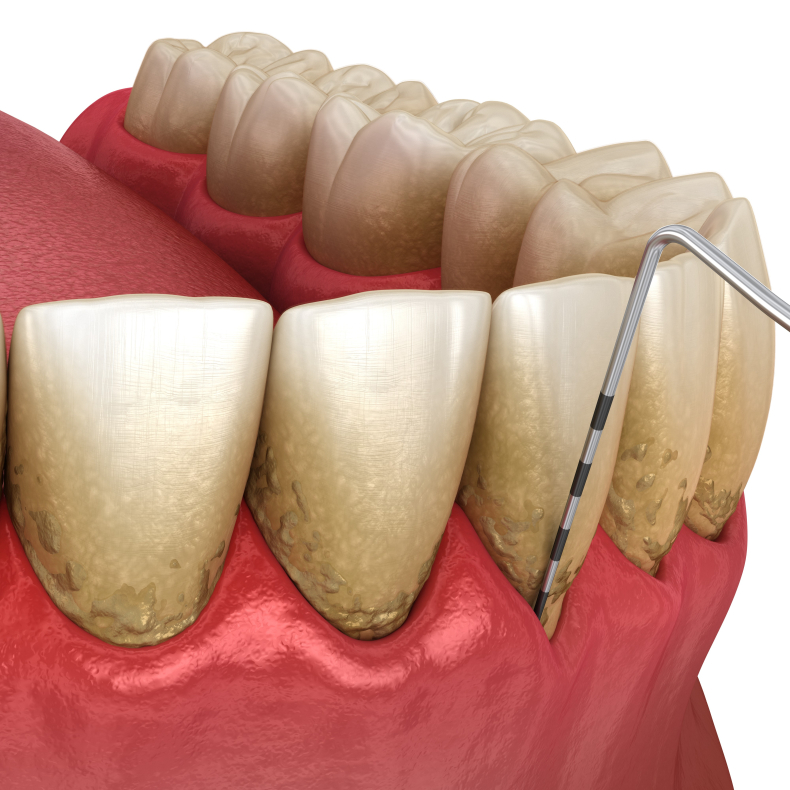

• Systematisk journaloptag, risikovurdering og kliniske målinger

• Røntgenanalyse og vurdering af sygdomsprogression